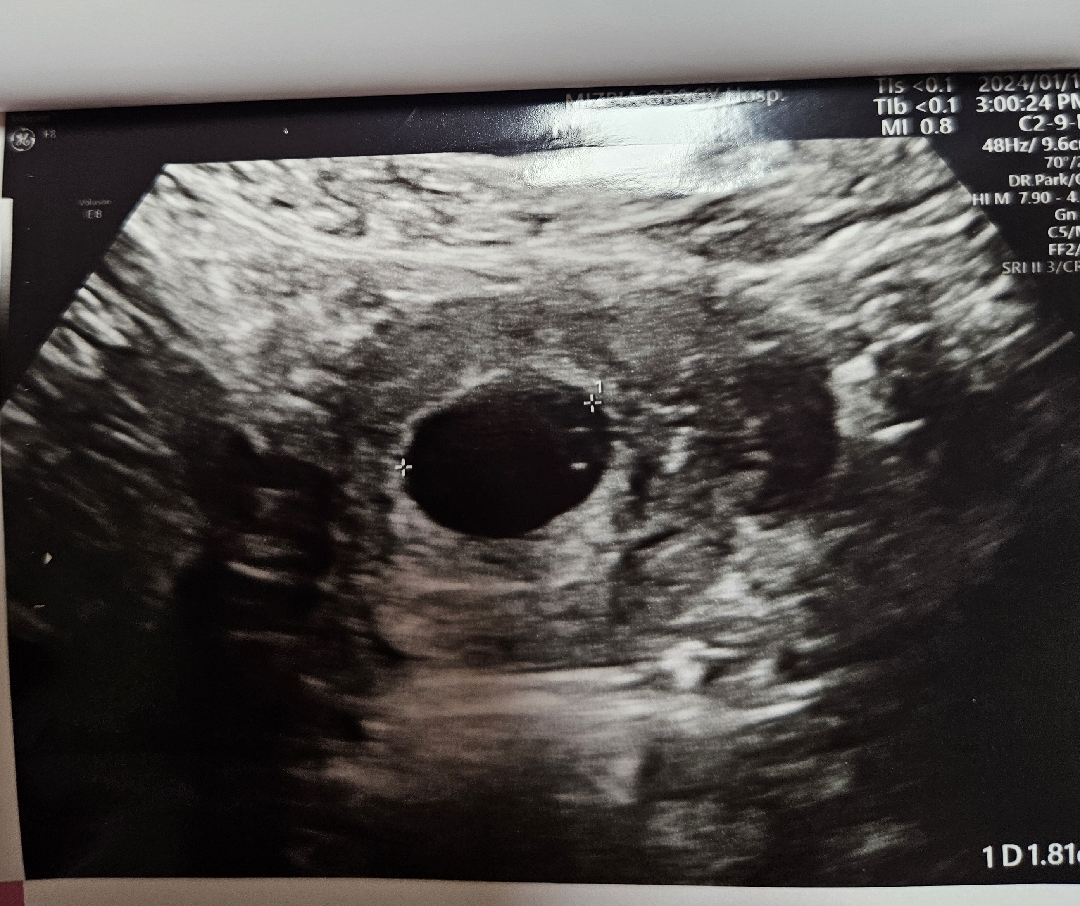

5주4일차 아기집 보고왔어요

오늘 입덧이 심해서 입덧약처방 겸 첫 진료봤어요! 1월2일에 임테기로 두줄확인했지만 네이버주수로 3주4일차로 나와서 극극극초기라 아기집도 안보일테니...2주정도 기다렸어요!! 근데 아기집 크기보시고는 5주4일로 보시더라구요!네이버주수로는 현재 4주6일차였는데 좀 차이는 있는것같아요!!!!!!!!!